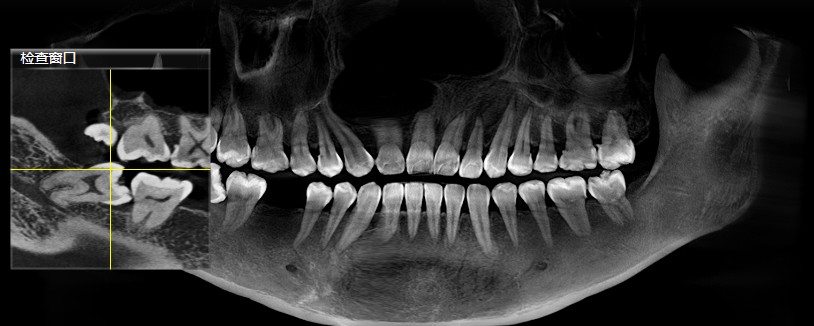

智齿位置、结构、生长形态各不相同,这也直接导致拔除的难易程度各不相等。一些长得比较"正"智齿,它的拔除过程相对比较轻松,且操作比较简单,耗材也较少,所以收费也就不会太高。但有一些智齿,它是倾斜长的,或者是水平长的,或者是埋在骨头里的,甚至压着神经管的,这种智齿拔除手术的难度和医生的操作要求都相对较高,因此价格也会相应地提升。